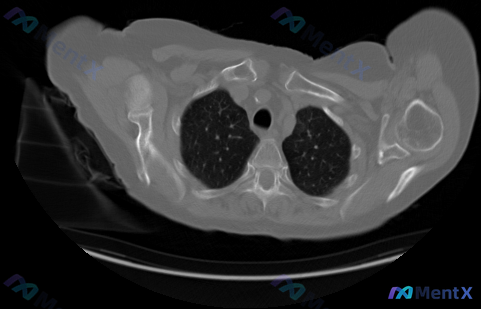

刚看到一个很有意思的案例——临床直接问“图片中显示的癌症的类型和分期是什么”,但拿到手的只有一张胸部CT骨窗横断面。 先把这张影像的客观所见理清楚: - 骨骼结构:胸椎椎体、附件、双侧肋骨、锁骨、肩胛骨及肱骨头近端皮质均连续,未见明确骨质破坏、硬化灶或骨膜反应;骨小梁纹理尚可,椎体无楔形变。 - 软...